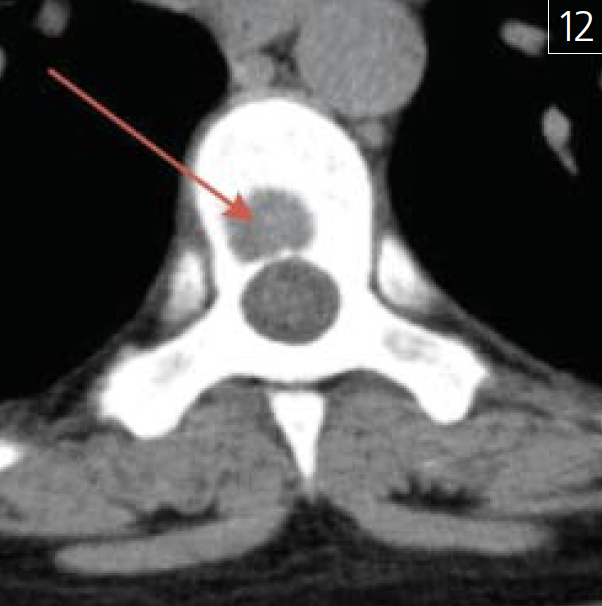

Печальной находкой в практике врачастоматолога и челюстно-лицевого хирурга могут стать остеолитические метастазы в кости скелета, в т.ч. в позвонки (рис. 12).

Рис. 12. Участок деструкции костнойткани тела позвонка с неровными,нечеткими контурами и минимальнойкаймой склероза (указан красной стрелкой)